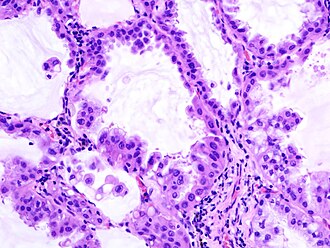

Mucini su glikoproteini velike molekulske mase koju čine dugi polipeptidni lanac i mnogobrojni kratki oligosaharidni pobočni lanci.

Sastavni su dijelovi tjelesnih sluzi. Mnoge ugljikohidratne grupe mogu vezati vodu, čime se objašnjava njihova sluzavost.